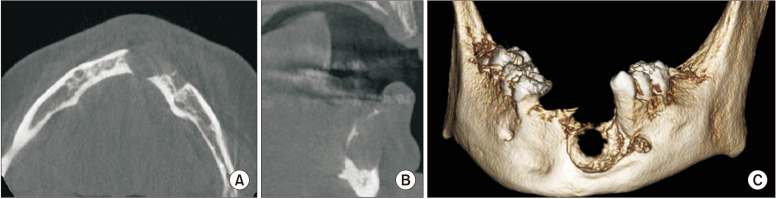

Neurofibromatosis type 1 (NF1) is an autosomally dominant tumor suppressor syndrome and multisystem disease. Central giant-cell granulomas (CGCGs) can be seen in patients with NF1. A 21-year-old female was diagnosed with two CGCGs, one in the mandible and then one in the maxilla, in a 7-year period. Increased incidence of CGCGs in NF1 patients was thought to be caused by an underlying susceptibility to developing CGCG-like lesions in qualitatively abnormal bone, such as fibrous dysplasia. However, germline and somatic truncating second-hit mutations in the NF1 gene have been detected in NF1 patients with CGCGs, validating that they are NF1-associated lesions. Oral manifestations in patients with NF1 are very common. Knowledge of these manifestations and the genetic link between NF1 and CGCGs will enhance early detection and enable optimal patient care.